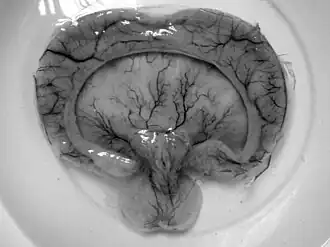

L'holoprosencéphalie, holoproencéphalie ou HPE est une malformation congénitale du cerveau. Elle consiste en la séparation anormale du cerveau primitif ou télencéphale en deux hémisphères et deux ventricules.

L'holoprosencéphalie (HPE) est une anomalie structurelle du cerveau normalement divisé en deux hémisphères droit et gauche. Dans l'HPE, cette séparation ne se fait pas ou reste incomplète d'où l'existence de différents types d'HPE formant un continuum de malformations (les différents types ne se distinguent pas par des limites précises, ils forment un ensemble continu)[6].

HPE alobaire

C'est la forme la plus sévère avec absence totale de scissure longitudinale et un ventricule cérébral unique (les deux ventricules latéraux du cerveau sont restés fusionnés en un seul)[2].